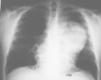

Radiología Casos en imagen 2

Casos en imagen 2

Case 2

J. Cubero Carraleroa, JM. Abadal Villayandrea, V. Guadaño Salvadoresa

a Servicio de Radiodiagnóstico. Hospital Severo Ochoa. Madrid. España.